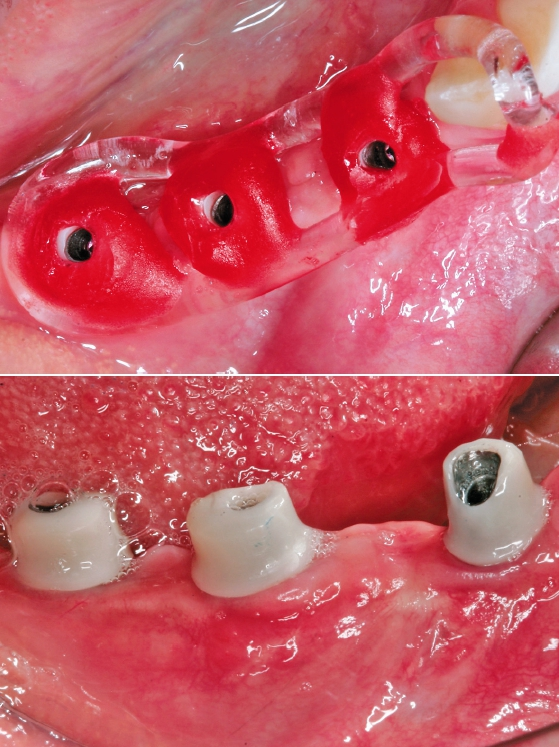

Der Lappen wurde reponiert und mit nicht resorbierbarem Nahtfaden der Stärke 4.0 adaptiert. Um einen spannungsfreien Wundverschluss zu erreichen, wurde apikal eine laterale Matratzennaht gesetzt. Die Nähte wurden nach 14 Tagen entfernt. Nach sechs Monaten komplikationsfreier Wund- und Einheilung kam die Patientin zur Implantatbehandlung erneut in die Praxis (Abb. 6 und 7). Beim Re-Entry wurden die Befestigungsschrauben entfernt, und es wurde eine Knochenkernbiopsie für die histologische Analyse entnommen (Abb. 8 und 9). Die histologische Untersuchung der mit Hämatoxylin-Eosin eingefärbten Schnittpräparate der Probe zeigte den laufenden Umbauprozess des FDBA-Blocks. Die histologische Aufnahme (Abb. 10) zeigte neu gebildeten Geflechtknochen (WB) in engem Kontakt mit dem Allograftmaterial (*) und umgeben von Bindegewebe (CT) und belegte die durch das Allograftmaterial vermittelte Knochenregeneration. Nach Bestimmung der geeigneten Implantatpositionen wurden in regio 47, 46 und 44 drei Bone Level Implantate Straumann® BLX Roxolid® SLActive ® mit einem Durchmesser von 4,5 mm und einer Länge von 10 mm gesetzt (Abb. 11 bis 14). Die Implantate wurden mit RB Verschlusskappen verschlossen, der Wundverschluss erfolgte mit Nahtmaterial der Stärke 4.0 (Abb. 15 und 16).

Nach drei Monaten wurden die Implantate mit einer krestalen Inzision freigelegt. Die Verschlusskappen waren teilweise bereits von neu gebildetem Knochengewebe überwachsen (Abb. 17). Dies zeigt das vitale Potenzial des Knochengewebes, das sich in diesem Bereich neu gebildet hatte. In die Implantate wurden RB/WB Gingivaformer (Ø 5 mm, Gingivahöhe 1,5 mm) eingesetzt, die Weichgewebe wurden um die Gingivaformer reponiert und mit nicht resorbierbarem Nahtmaterial der Stärke 5.0 vernäht (Abb. 18 bis 20).